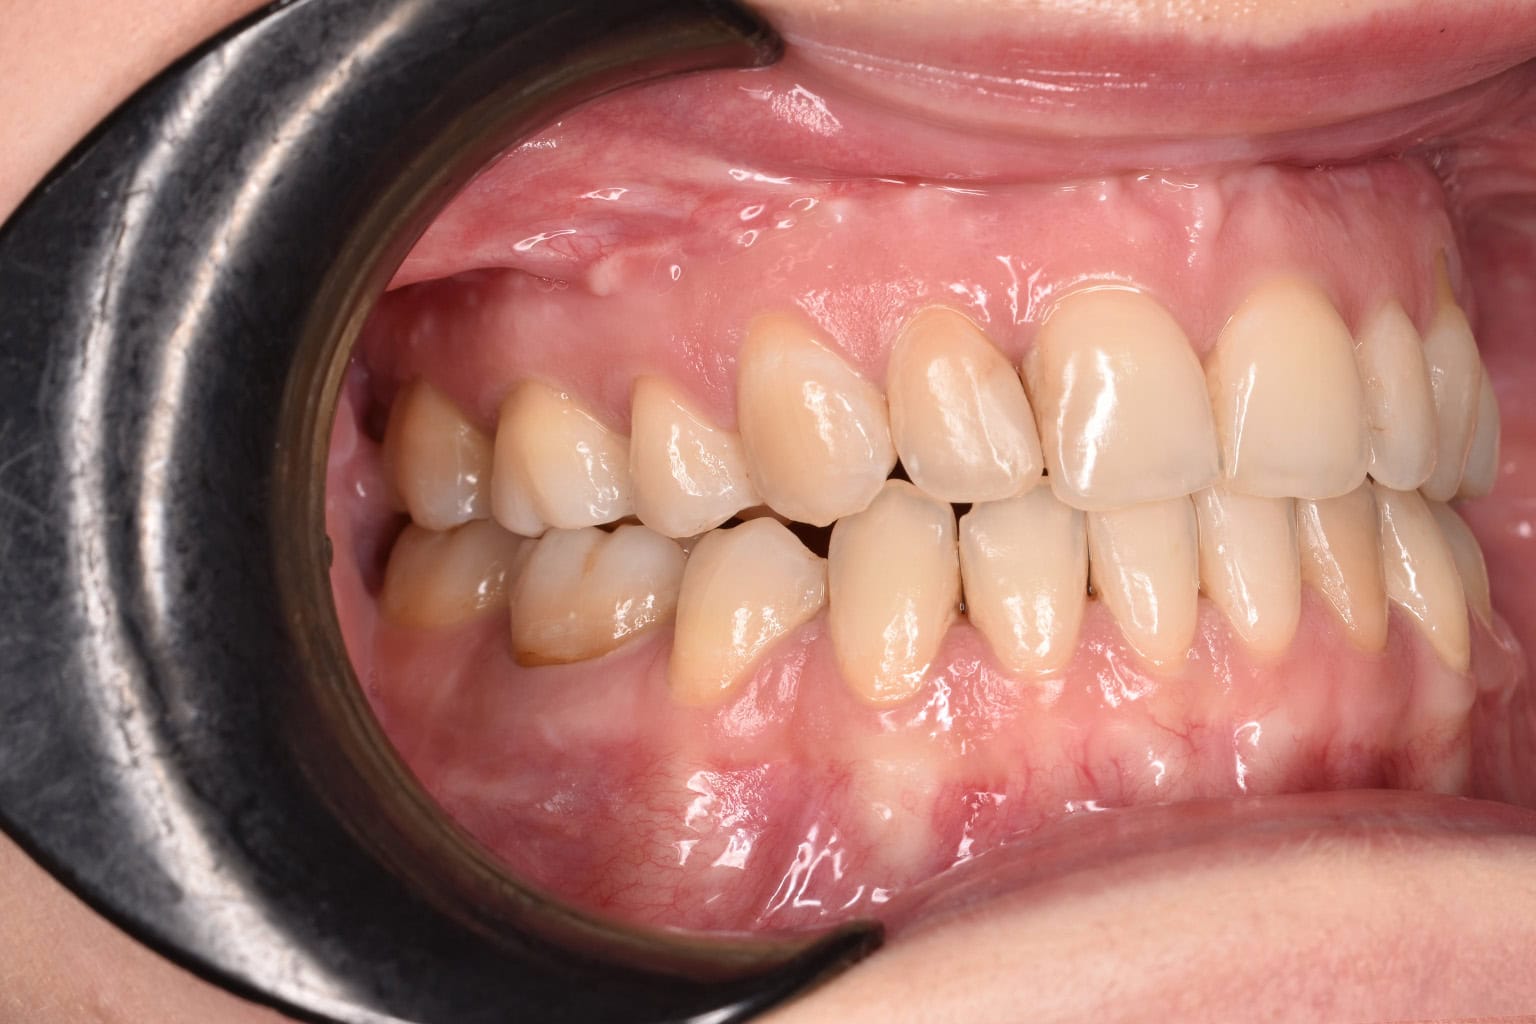

Vorher-Nachher-Ergebnisse

Echte Ergebnisse. Echte Menschen.

Jede Behandlung bei TIEFBLAU Kieferorthopädie ist so individuell wie der Mensch dahinter. In unserer Vorher-Nachher-Galerie zeigen wir Ihnen echte Behandlungsergebnisse aus unserer Praxis in der Kölner Südstadt: Schonend erzielt, präzise geplant und mit dem Anspruch, den wir seit über 40 Jahren an jede Behandlung stellen.

Die Bilder geben Ihnen einen Eindruck davon, was moderne Kieferorthopädie leisten kann, ob bei Kindern, Jugendlichen oder Erwachsenen.

Der sichtbare Unterschied

Dokumentiert. Überzeugend. Nachhaltig.